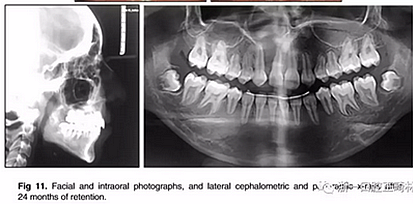

治療持續(xù)3年,患者始終保持積極和合作??谇恍l(wèi)生很好。患者和她的父母都對(duì)結(jié)果感到滿意。經(jīng)過24個(gè)月的保持后,咬合保持得很好(圖11 ; 圖12)。在上牙弓中,應(yīng)用固定舌側(cè)保持器以防止任何復(fù)發(fā)傾向。在下牙弓中,治療后拔除第三磨牙。